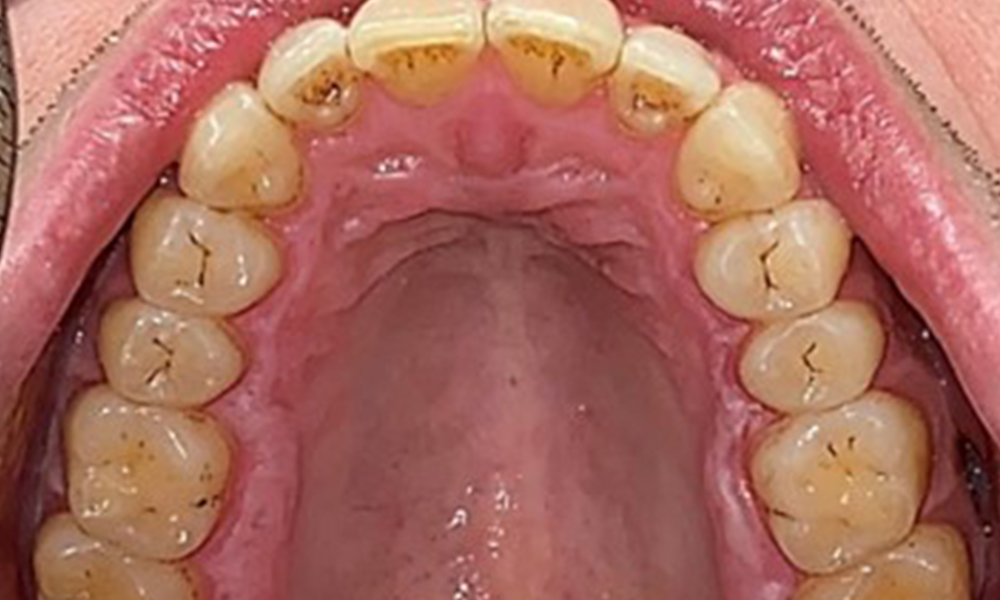

There were no pathological extraoral findings. During intraoral examination, inspection of the frontal view revealed brownish discolouration near the keratinised gingiva and at the transition to the moveable mucosa (Fig. 2), which could be attributed to nicotine consumption. Whitish mucosal lesions were observed on the palate, particularly near the maxillary molar palatal surfaces, indicating increased keratinisation and can also be attributed to nicotine consumption. The tongue was covered with a removable white and brownish coating.

The patient has full dentition with a total of 28 teeth. There were noteworthy erosions and attritions. (Fig. 4, Fig. 5). Due to bruxism, the patient has been wearing a splint with an adjusted bite block at night for many years. The erosions were caused by long-term consumption of isotonic beverages. No periodontal bone loss or active caries were observed.

Full complement of adult teeth with no caries or radiologically recognizable bone loss was observed (Fig. 6). Radiological enamel and cusp loss were particularly evident on 36 and 37.